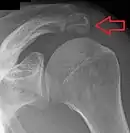

Épaule

Un os acromial se forme lorsque l'un de ses quatre centres d'ossification ne parvient pas à fusionner. Ces quatre centres d'ossification sont appelés de la pointe à la base pré-acromion, méso-acromion, méta-acromion et basi-acromion. Dans la plupart des cas, les trois premiers fusionnent entre 15 et 18 ans, tandis que la partie de base fusionne avec la colonne scapulaire à 12 ans. Un tel échec de fusion se produit dans 1 à 15 % des cas[15],[16]. Cela provoque rarement une douleur.